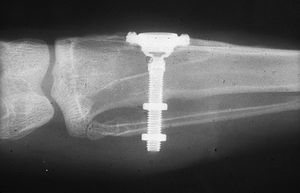

اذا كان العظم على استعداد لتلقي الزرع (أحيانا بعد سلسلة علاجات مسبقة)، يمكن البدء بعملية زرع الاسنان. يتم تثبيت المسامير المعدنية اللولبيه براغي، بعظم الفك. في سلسلة اخرى من العلاجات بعد فترة من ادخال البراغي، تبدا عمليات اعادة البناء عن طريق أخذ القياسات وانشاء التاج/الجسر. عندما يدور الحديث عن فترة الانتظار بين تركيب الغرسات وبين تنفيذ الاستبناء النهائي، فان هنالك اكثر من نهج واحد. النهج المتبع غالبا هو الانتظار لمدة 6 أسابيع على الأقل حتى تلتئم الانسجة، وأحيانا تصل فترة الانتظار لعدة شهور.

وأخذ النوع الرابع شأنه الكبير في الستينات من القرن العشرين، وكان ستروك (1939) أول من قام بغرس لولب في العظم للتعويض عن سن مقلوعة.

في عام 1962 غرس شيرشيڤ لولباً من التيتانيوم في العظم، وفي عام 1971 حول هاينريش مادة اللولب إلى التانتال في الوقت الذي قام فيه ساندهاوس بتجربة غرسة أكسيد السيراميك ceramic oxide أما سيالوم (عام 1962) فقد جعل الغرسة ثلاثة جذور متباعدة من التانتال.

من عيوب الغرسات داخل العظم مساحة سطحها المحدودة في تماسها مع العظم وبالتالي نقلها الضغط عند المضغ إلى مساحات محدودة من العظم، علماً بأن ثبات الغرسة يكون أكبر ونجاحها أعظم، كلما كان سطح تماسها مع العظم أوسع، ولذلك قام لينكوڤ عام 1966 بصنع شفرات من التيتان أسماها بالغرسة الانبساطية، وقد أضاف إليها هاينريش عام 1976 مخالب جانبية تجعل الغرسة خليطاً من الشكلين الثالث والرابع.

في عام 1976 صنع كوخ الغرسة الأسطوانية، وتمتاز بما يلي:

- تحضير الفتحة العظمية سهل إذ يتم بوساطة سنبلة خاصة مما يحقق تماساً جيداً بين الغرسة والعظم.

- يمكن فصل الجزء البارز خارج العظم عن الغرسة بحركة لولبية مما يحقق لمنطقة الغرسة المغلقة تحت الغشاء المخاطي والسمحاق شفاء جيداً.